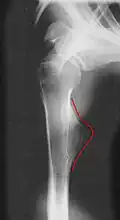

Die Begriffe Osteochondrom, Ekchondrom und kartilaginäre Exostose beschreiben gutartige Knochentumoren. Solange der Tumor nicht verknöchert ist, spricht man vom Ekchondrom oder kartilaginärer Exostose. Als Osteochondrom wird der Tumor nach Verknöcherung bezeichnet. Diese Tumoren wachsen gestielt vom gelenknahen Knochen (Metaphyse) aus. Es sind die häufigsten gutartigen Knochentumoren. Sie machen sich meistens durch Wachstum im Kindesalter bemerkbar. Nach Abschluss des Knochenwachstums im Erwachsenenalter wachsen die Tumoren meist nicht weiter.

Symptome sind selten und treten nur auf, wenn der Tumor auf andere Strukturen wie etwa Nerven oder Gefäße drückt oder die Gelenkbewegung behindert. Der Tumor ist meist nicht druckschmerzhaft. Eine Behandlung ist nur bei Beschwerden notwendig und besteht in einer möglichst vollständigen operativen Entfernung. Verlauf und Prognose sind gut, eine bösartige Entwicklung ist selten.